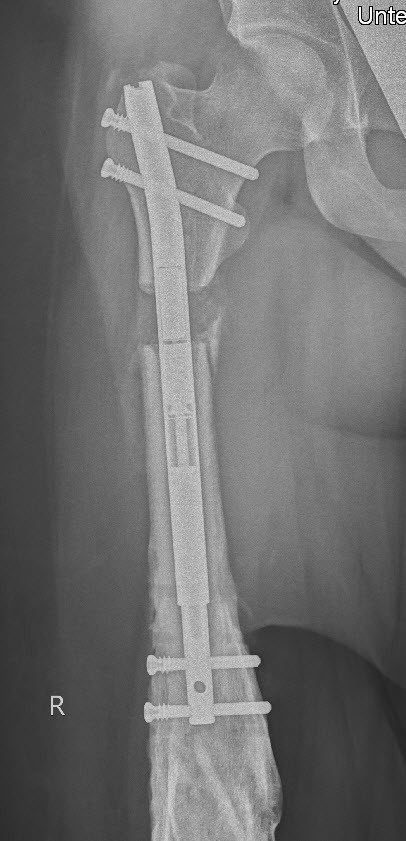

Aufgrund der nun noch persistierenden Beinlängendifferenz entschlossen wir uns zu einer Verlängerung des Oberschenkelknochens mit dem magnetgetriebenen Precice®-Marknagel. So konnten wir den Oberschenkel schlussendlich mit diesem Nagel problemlos um 3.5 cm verlängern (Bild 3).